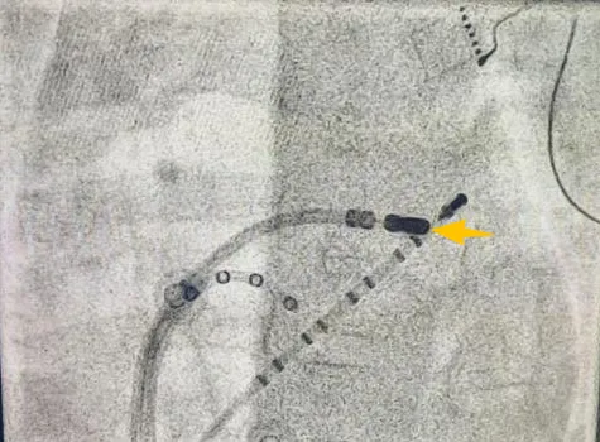

通常情况下,成人选用逆行主动脉法(经股动脉、主动脉瓣)将消融导管送达“短路”区域,但损伤患儿大动脉和主动脉瓣风险高,团队另辟蹊径:穿刺房间隔,经左心房顺行途径消融“短路”区,需要小心谨慎穿刺房间隔,在左心房内稳定操作消融导管,精细定位“短路”区,消融成功,安全、精准地“拆解”了心内异常电路。

X线影像,消融靶点,黄色箭头